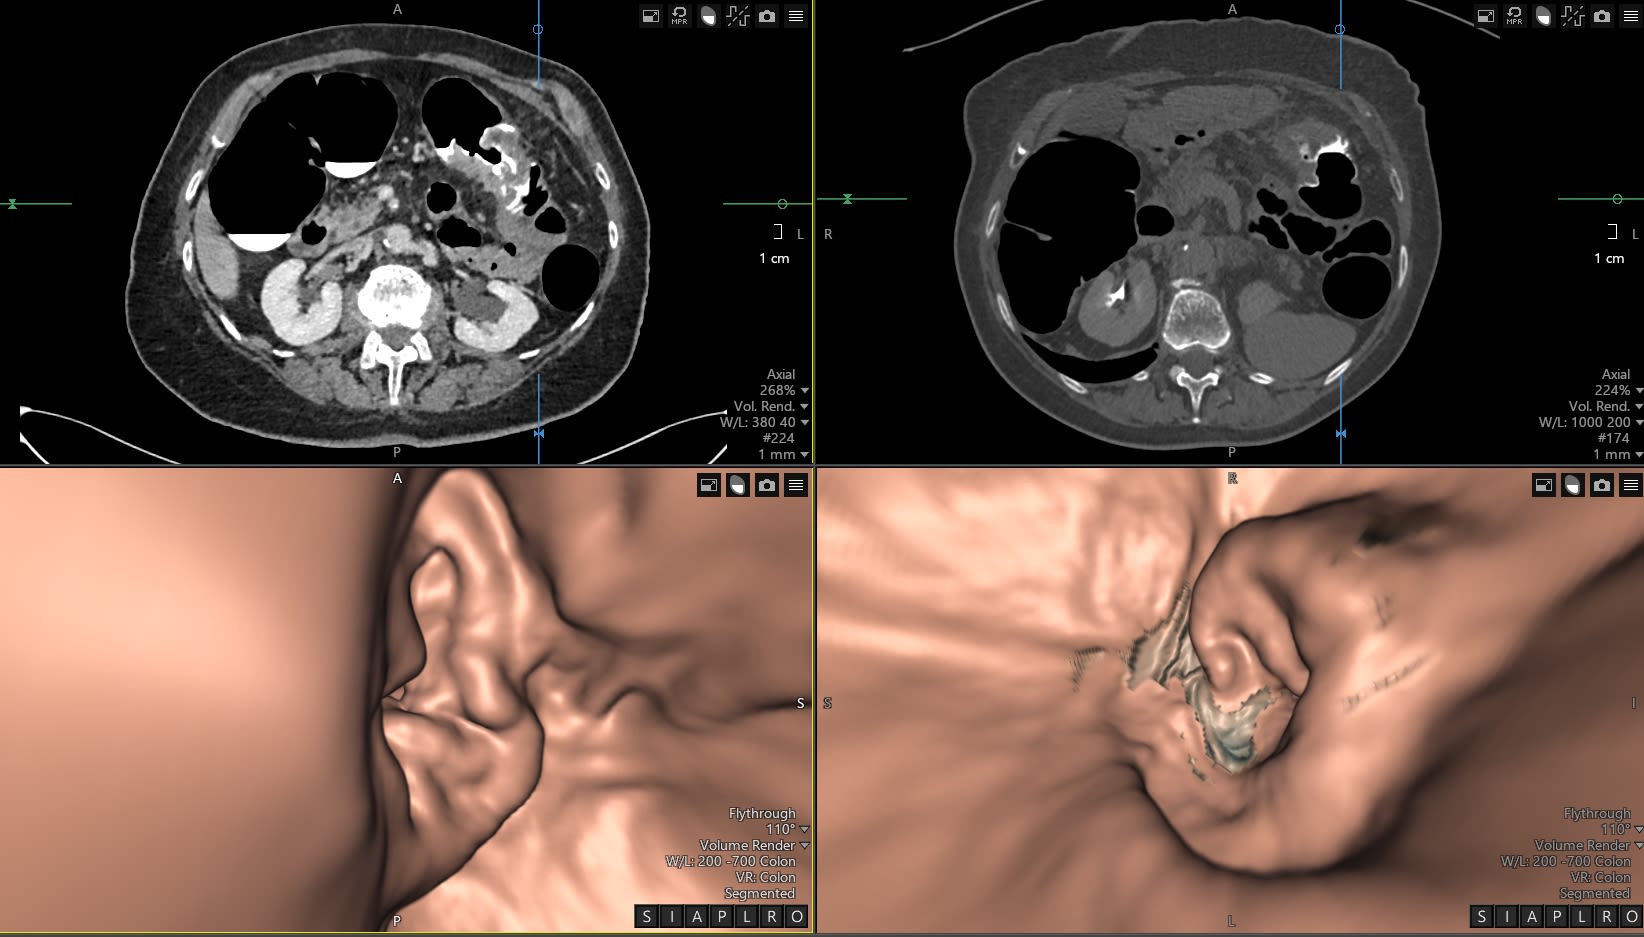

CT Colonography scan supine and prone views - showing a large circumferential transverse colon cancer

CT colonography is highly sensitive for detecting colorectal cancer and polyps, although reporter competency has a major influence on test accuracy.

Research has shown that if the test is not performed well to recommended guidelines, and the person reporting it is not well trained, then pathology is missed which ultimately is detrimental to patient outcomes.